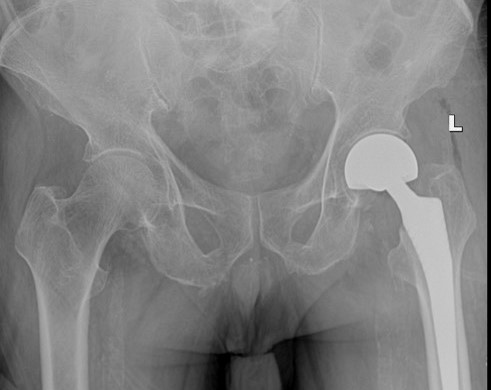

- Hình ảnh sau mổ của bệnh nhân

Với sự chuẩn bị kĩ càng và đầy đủ trước mổ cùng trình độ chuyên môn cao của phẫu thuật viên, sự phối hợp đồng bộ nhiều chuyên khoa mà ca mổ đã diễn ra rất thành công. Ngay sau mổ bệnh nhân đã có thể ngồi dậy tại giường, vận động hai chân tốt, tránh được các biến chứng nguy hiểm. Sau mổ bệnh nhân đau ít, vết mổ liền tốt.